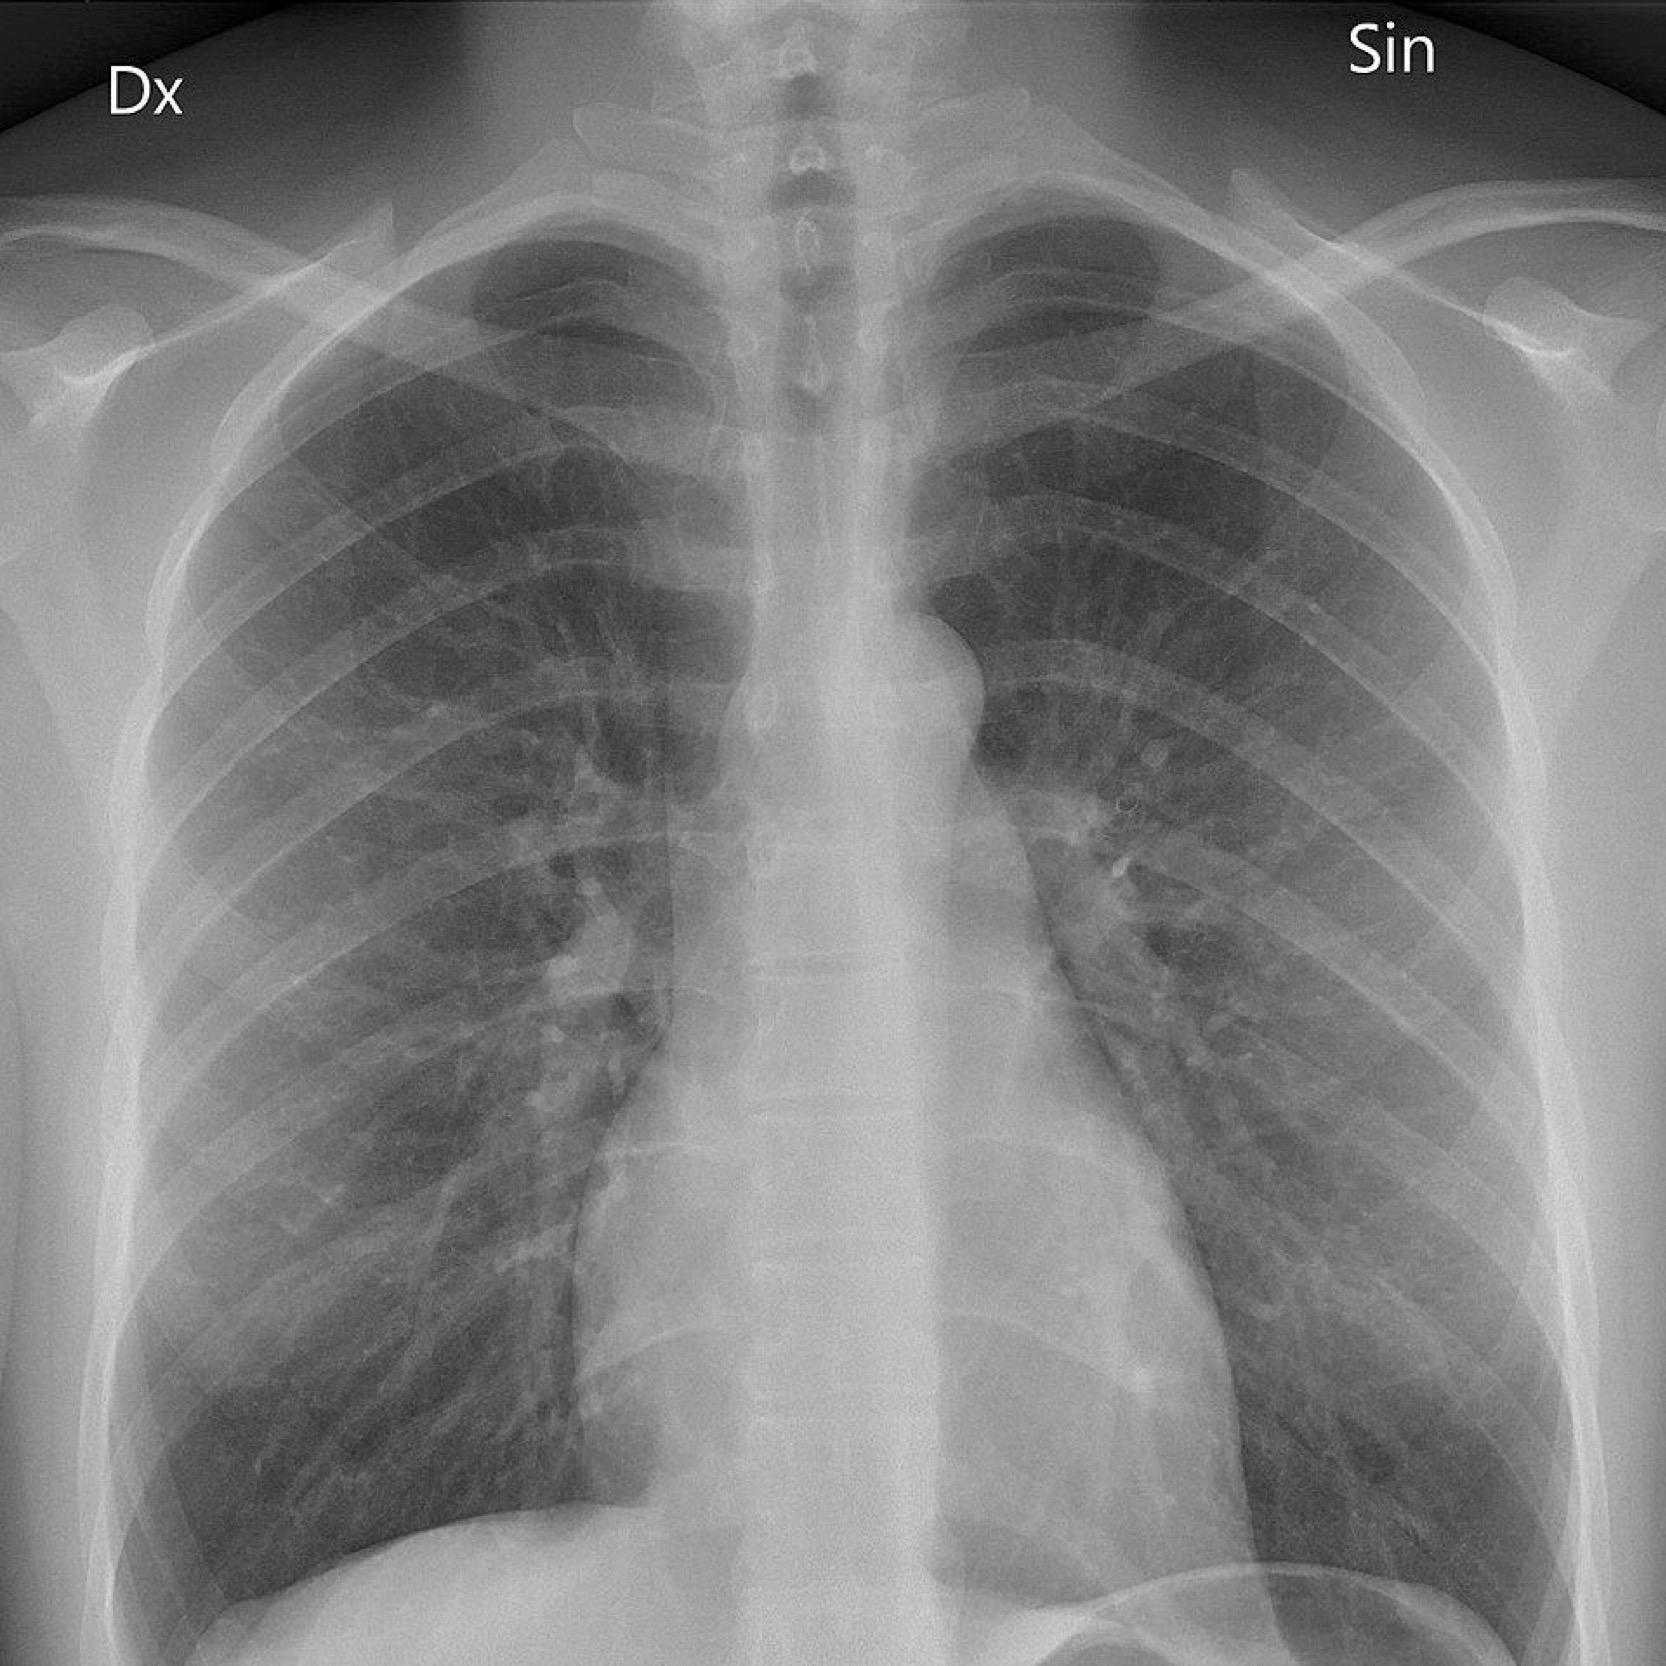

a Research Engineer and PhD candidate building AI systems that ensure fairness in medical imaging foundation models

Medical AI systems trained on biased datasets can yield disparate diagnostic accuracy across demographic subgroups, disproportionately affecting underrepresented populations. My research develops foundation models with fairness-aware training strategies to achieve equitable performance across patient demographics.

FairMI Project

Developing fairness frameworks for medical imaging foundation models (FairMI project, FAPESP-SNSF). Using self-supervised learning and distributed training on HPC. Published at MICCAI 2024 and ECCV 2024. Brazil-Switzerland collaboration.